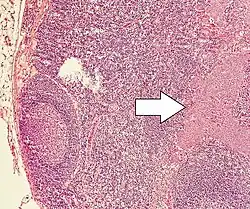

Micrograph of a neuroendocrine tumor. H&E stain. | |

NETs are often small, yellow or tan masses, often located in the submucosa or more deeply intramurally, and they can be very firm due to an accompanying intense desmoplastic reaction. The overlying mucosa may be either intact or ulcerated. Some GEP-NETs invade deeply to involve the mesentery.[72] Histologically, NETs are an example of "small blue cell tumors," showing uniform cells which have a round to oval stippled nucleus and scant, pink granular cytoplasm. The cells may align variously in islands, glands or sheets. High power examination shows bland cytopathology. Electron microscopy can identify secretory granules. There is usually minimal pleomorphism but less commonly there can be anaplasia, mitotic activity, and necrosis.